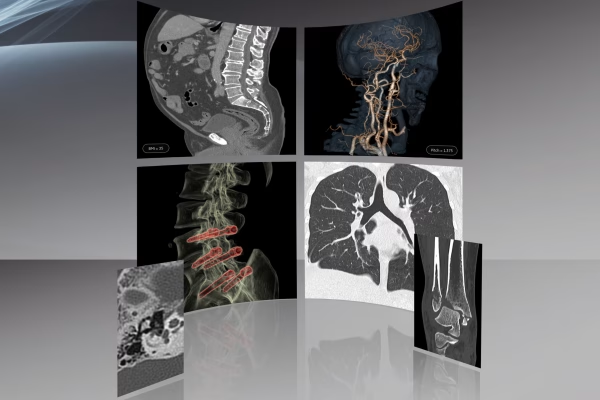

Notre service d’Imagerie Médicale et Radiologie Interventionnelle, un pilier essentiel de notre approche diagnostique. Avec une expertise avancée et une technologie de pointe, nous offrons une imagerie de haute précision pour éclairer votre parcours médical. Notre équipe de spécialistes dévoués s’engage à fournir des diagnostics fiables et des soins personnalisés, en mettant l’accent sur votre bien-être et votre satisfaction. Vous pouvez compter sur nous pour une expérience professionnelle et des résultats médicaux de qualité supérieure.

IRM GE Signa Explorer 1.5T

Scanner GE Optima CT520